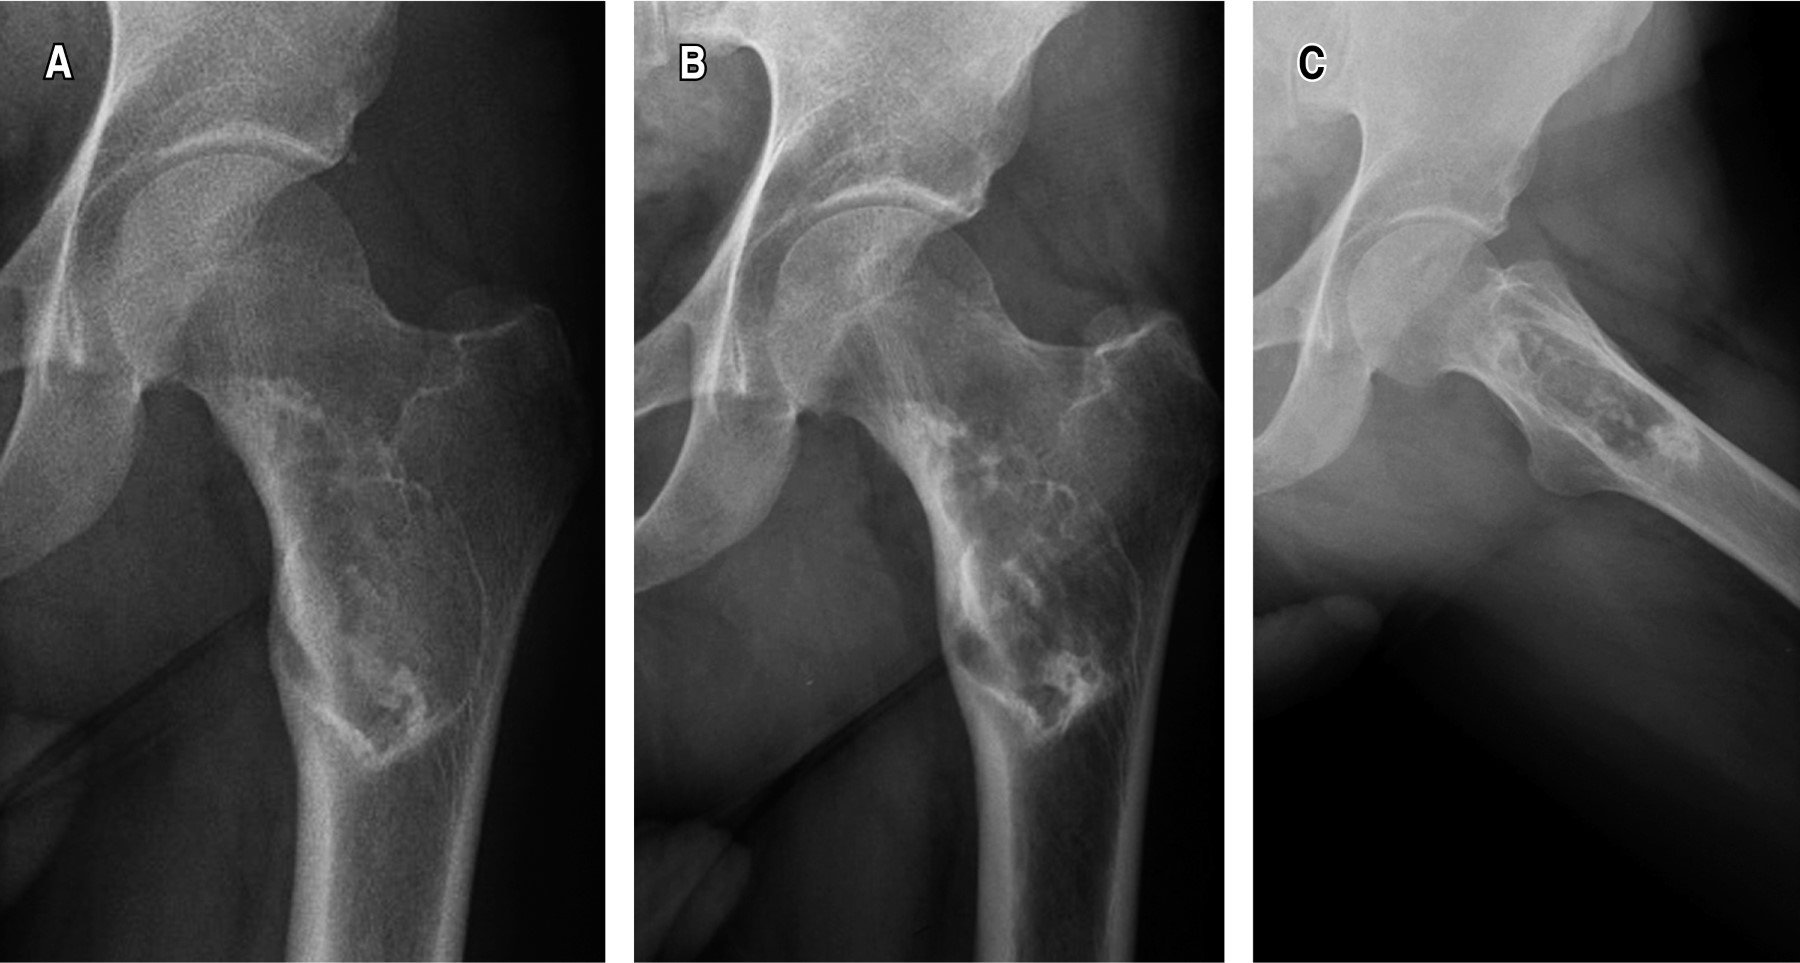

Liposclerosing myxofibroma of the proximal femur: diagnostic and therapeutic controversies. Apropos of 3 clinical cases

Introduction: The bone liposclerosing myxofibrous tumour (LSMFT) is a rare benign fibro-osseous tumor with characteristic clinical-radiological features, although its diagnosis and treatment are controversial. Material and methods: We present three patients, two women and one man, with a mean age of 46 years, diagnosed with LSMFT. The findings of the complementary imaging tests and the treatment performed are presented: observation in two patients and curettage, and the third patient was treated with curettage, grafting and surgical fixation. Results: The first two patients, after 10 and three years of follow-up, respectively, maintain the same symptoms and no progression of the lesion. Conclusions: The diagnosis of LSMFT can be assumed by clinical and imaging data without biopsy. In the absence of signs that suggest malignancy, observation is justified, limiting the surgical indication to symptomatic cases and/or those with risk of pathological fracture.

Figure 4

Figure 5